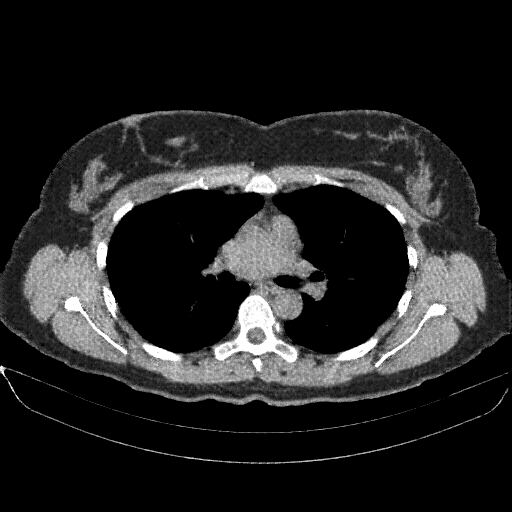

Image Grid

4Γ—3 grid: Rows show different image types (Original NATIVE, Reconstructed NATIVE, Original VENOUS, Generated VENOUS), Columns show windowing techniques (No Window, Lung Window, Mediastinum Window)

Reconstructed NATIVE CT scan (cycle consistency)

Lung window (WL -600, WW 1500 β†’ Low βˆ’1350, High +150)

Original VENOUS CT scan

Generated VENOUS CT scan (A→B translation)